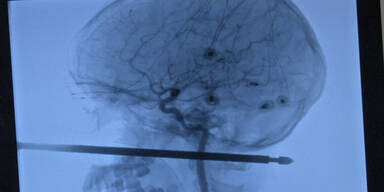

Der Spieß drang 15 Zentimeter tief in den Schädel ein.

Diesen hatten die Kinder zuvor senkrecht in den Boden gerammt, wie US-Medien berichteten. Der Spieß drang unterhalb des Auges durch Xaviers linke Wange und den Schädel. Das Kind rappelte sich auf und rannte nach Hause. "Ich habe ihn schreien gehört", berichtete Xaviers Mutter Gabrielle Miller der Zeitung "Kansas City Star". "Er kam rein und hatte dieses Ding in Gesicht stecken."

So etwas habe er noch nie gesehen, sagte Neurochirurg Koji Ebersole dem "Kanas City Star": "Dieses Ding ist knapp an seinem Auge, seinem Gehirn und seinem Rückenmark vorbeigegangen", sagte er über den Grillspieß. Es sei unglaublich, dass der Spieß 15 Zentimeter tief in den Schädel eingedrungen sei, ohne diese Gebiete zu treffen. Auch größere Blutgefäße seien glücklicherweise nicht beschädigt worden. Die Ärzte gingen davon aus, dass Xavier keine ernsteren Schäden zurückbehalten wird.